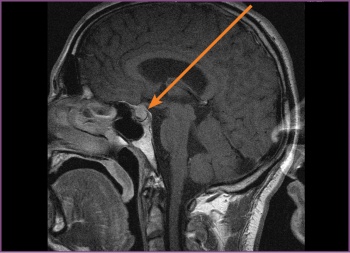

However, despite AZ’s normalised prolactin, his headaches persisted, hence an MRI of the brain, T1-weighted, was ordered. The MRI revealed a macroadenoma in the pituitary fossa, which extended into the suprasellar region compressing the chiasma, there was also dilatation of the third and lateral ventricles suggesting some degree of compression at the aqua duct (see Figure 1). AZ was discharged from the psychiatric unit on aripiprazole to follow up with the endocrinologist, who prescribed cabergoline 0.25mg twice weekly.

Figure 1: Pre-surgery, the first MRI, T1-weighted (sagittal) – the pituitary fossa shows a macroadenoma (11 mm)(click to enlarge)